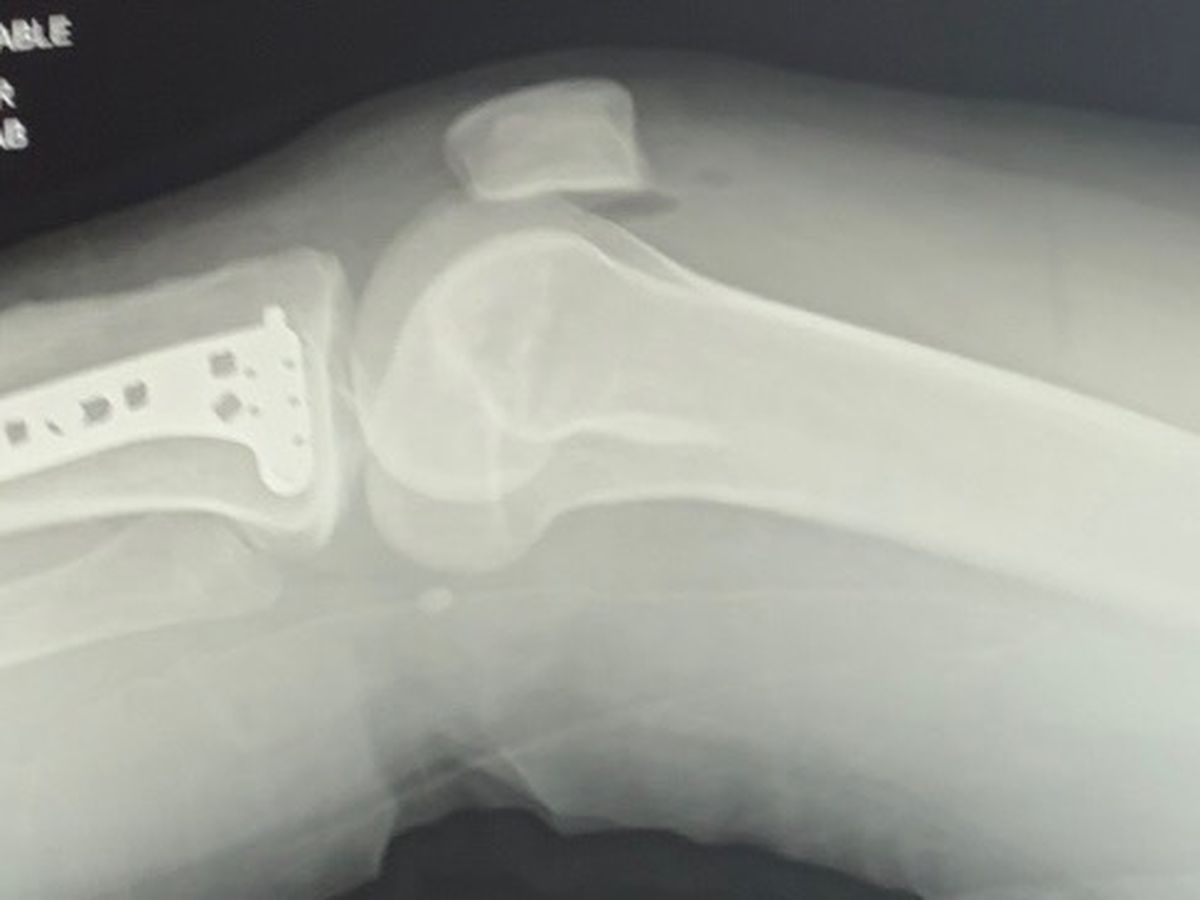

Devin is a month out from surgery and is tackling healing head-on just like she does life. She has learned how to get around her house by scooting herself backwards in her office chair with the walker on her lap, getting groceries delivered and carrying the bags in on a broom handle, and keeping herself entertained with her artistic expression. She is in a new brace; however, she is still having some blood flow/circulation issues they are monitoring.